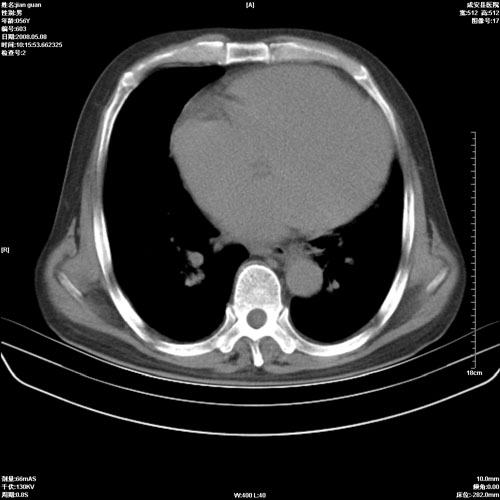

病人 男 60岁 主诉 胸闷 无明显发热 一般情况尚可。

考虑1心功不全,肺水肿

2右上肺结核纤维性病灶、肺气肿

1.右上肺陈旧性肺结核.

2.心脏增大(以左心室增大为著),请结合b超及听诊.

1.两上肺陈旧性结核;慢支肺气肿。

2.肺门血管扩张,心脏增大,为肺心病

考虑.两上肺陈旧性结核;慢支肺气肿。肺心病

1.陈旧肺结核;

2.慢支肺气肿;

3.肺心病.

陈旧性肺结核,左心房扩大,左心衰竭